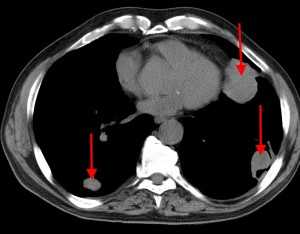

Слева - рак почки с метастазами в легкие, прогноз в данном случае неблагоприятный ввиду метастатического плеврита и дыхательной недостаточности. Определяются очаги с обеих сторон. Справа - мелко- и среднеочаговая диссеминация при раке печени.

КТ: метастазы в легких при раке молочной железы. На изображении справа красной звездочкой отмечен опухолевый узел в молочной железе, красными стрелками - область прорастания опухоли в грудную стенку. Синими звездочками отмечен карциноматозный плеврит — скопление жидкости в плевральной полости. Слева стрелкой отмечен вторичный узел.